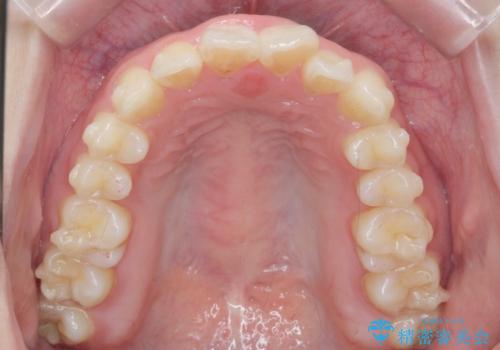

- ねじれの目立つ前歯の見た目を改善したいと矯正治療を希望され来院されました。

がたつきの改善をマウスピース矯正インビザラインで行っていきます。

ガタつきの改善はもちろん、歯列全体のアーチも放物線状にきれいに排列し審美性を向上させることができました。